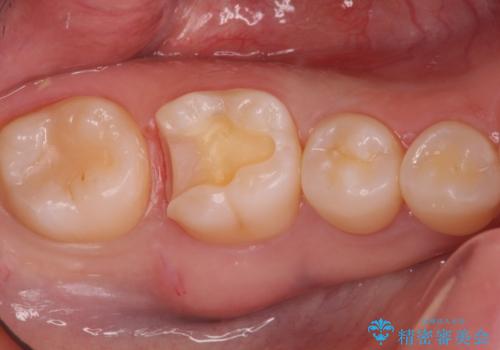

- 検査の結果虫歯が確認された患者様です。

見た目ではわかりにくい虫歯ですが、レントゲン画像でははっきりと写っていました。

まだ虫歯の大きさが小さいためインレーでの修復処置を行います。

虫歯が大きくなりきる前に治療を行えたため、歯の削る量を抑えることができました。